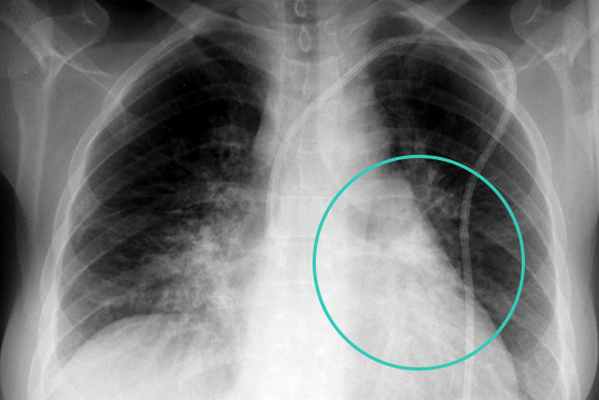

Специальные исследования • Рентгенография грудной клетки в двух проекциях •• треугольной формы интенсивная однородная тень с чёткими границами, с вершиной, направленной к корню лёгкого, с уменьшением объёма поражённого участка лёгкого •• При ателектазе доли или лёгкого — стойкое смещение средостения в больную сторону, купол диафрагмы на стороне поражения поднят, межрёберные промежутки сужены •• диффузные микроателектазы — ранее проявление кислородной интоксикации и острого респираторного дистресс-синдрома: картина «матового стекла» •• округлый ателектаз — округлое затенение с основанием на плевре, направленное к корню лёгкого («кометообразный» хвост из сосудов и воздухоносных путей). Чаще возникает у больных, контактировавших с асбестом, и напоминает опухоль •• правосторонний среднедолевой и язычковый ателектазы сливаются с границами сердца на этой же стороне (симптом Арман-Делиля) • Бронхоскопия показана для оценки проходимости дыхательных путей • ЭхоКГ для оценки состояния сердца при кардиомегалии • КТ или МРТ органов грудной полости.

В этой ситуации на обзорной цифровой рентгенограмме вы видите классическую картину ателектаза нижней доли левого легкого. В этом случае контур спавшей левой доли находится внутри от контура сердца. Естественно, исчезает нормальное изображение купола диафрагмы, реберно-диафрагмального синуса. А при томографическом исследовании – округлой формы с четкими контурами гиперваскулярное образование в корне левого легкого и типичный ателектаз нижней доли левого легкого с расширенными бронхами.

В этом случае наблюдаем картину формирования в течение нескольких месяцев полного ателектаза верхней доли левого легкого (здесь это хорошо показано стрелками).